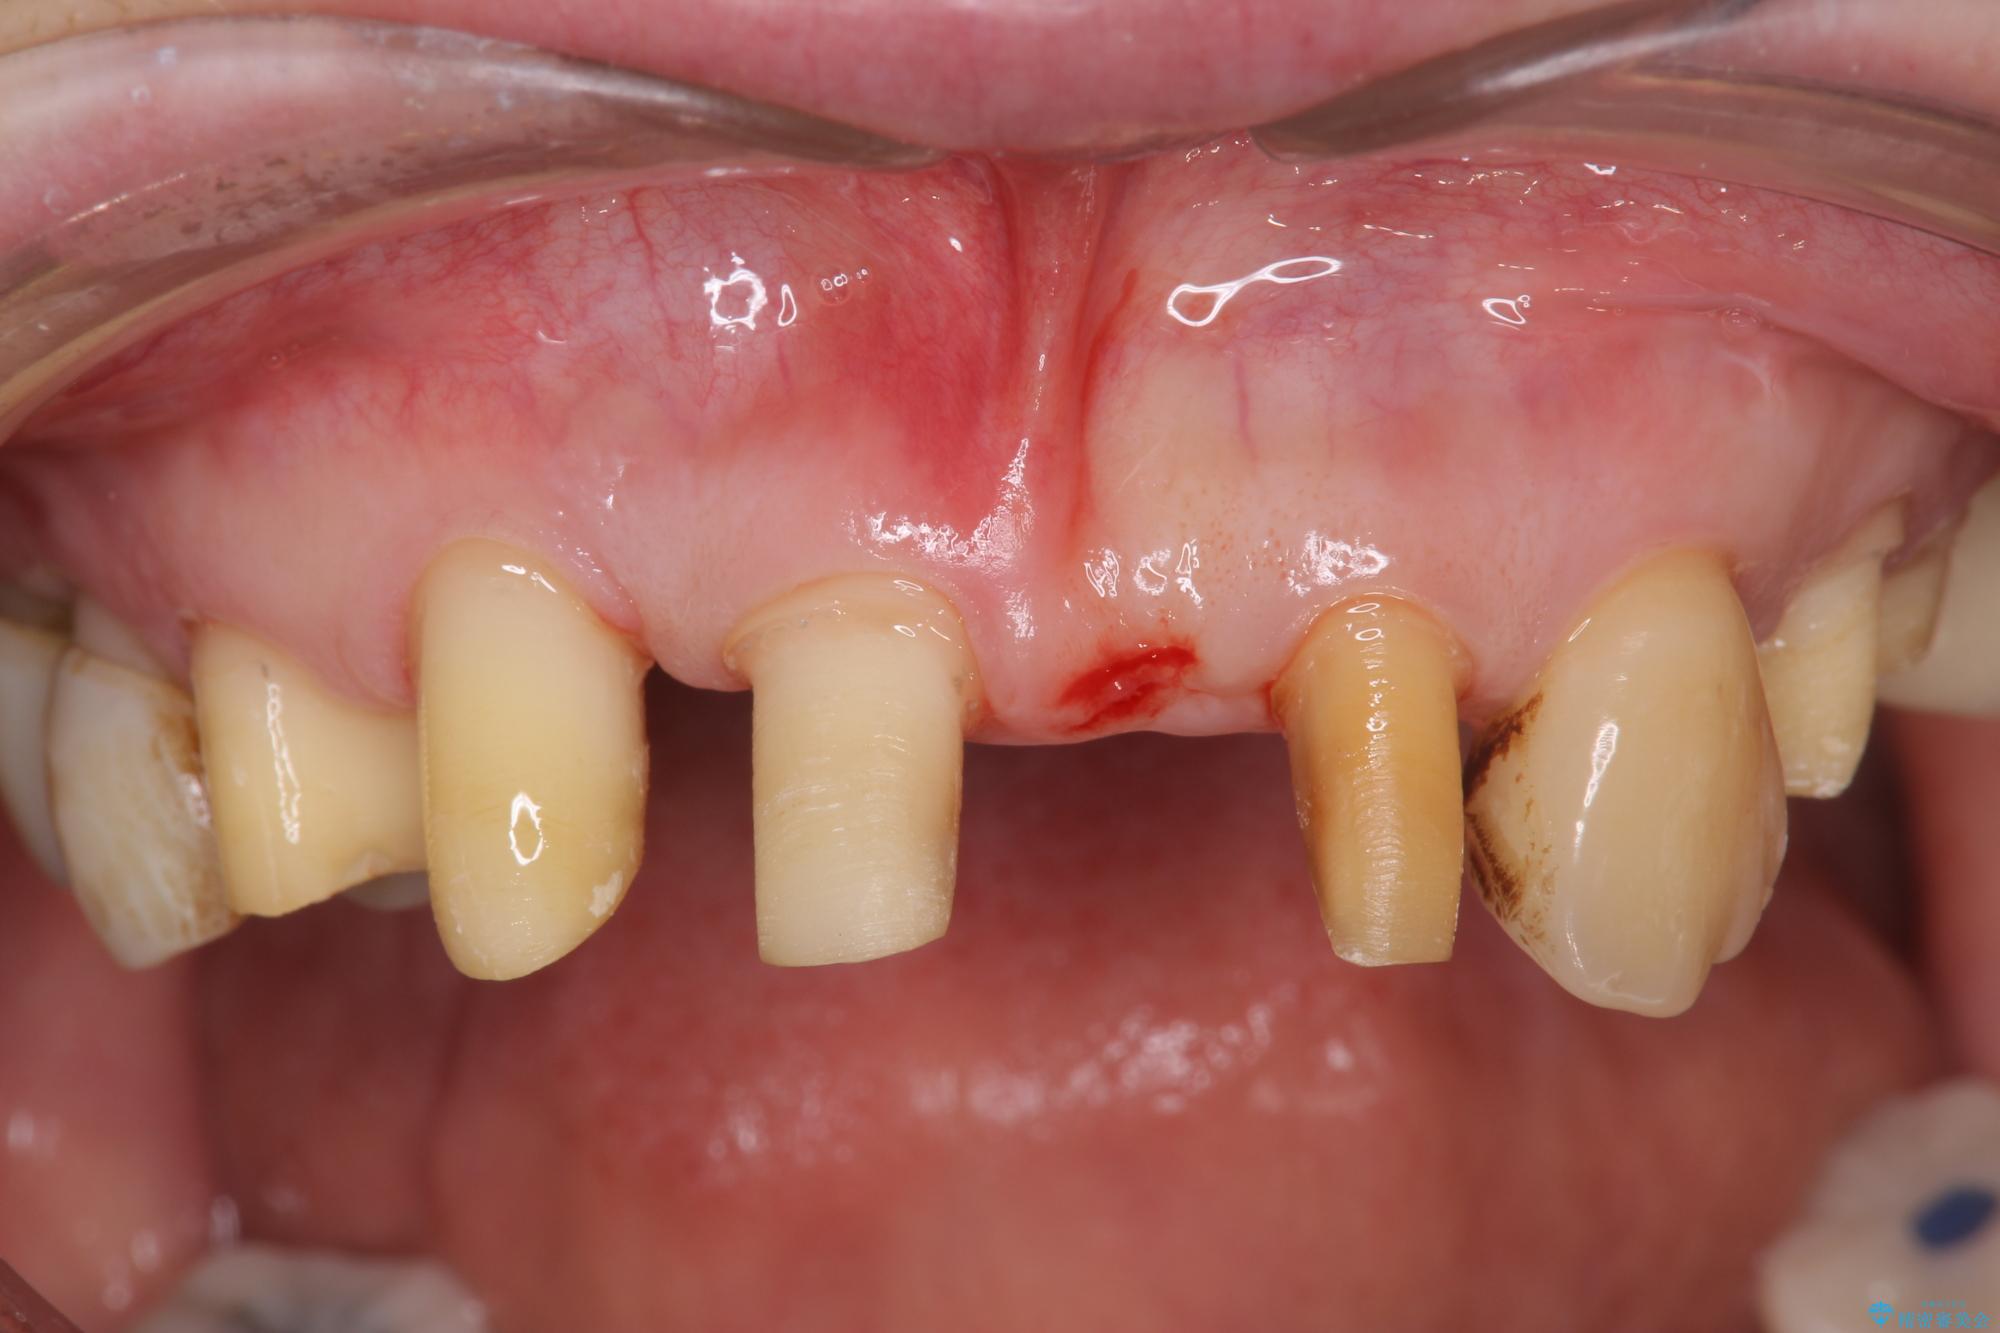

治療前

歯の総合的なマネージメントを行う包括的歯科治療の実践[ 歯周病・矯正・セラミック補綴 ] 治療前画像 歯の総合的なマネージメントを行う包括的歯科治療の実践[ 歯周病・矯正・セラミック補綴 ] 治療前画像 歯の総合的なマネージメントを行う包括的歯科治療の実践[ 歯周病・矯正・セラミック補綴 ] 治療前画像 歯の総合的なマネージメントを行う包括的歯科治療の実践[ 歯周病・矯正・セラミック補綴 ] 治療前画像 歯の総合的なマネージメントを行う包括的歯科治療の実践[ 歯周病・矯正・セラミック補綴 ] 治療前画像 歯の総合的なマネージメントを行う包括的歯科治療の実践[ 歯周病・矯正・セラミック補綴 ] 治療前画像 歯の総合的なマネージメントを行う包括的歯科治療の実践[ 歯周病・矯正・セラミック補綴 ] 治療前画像